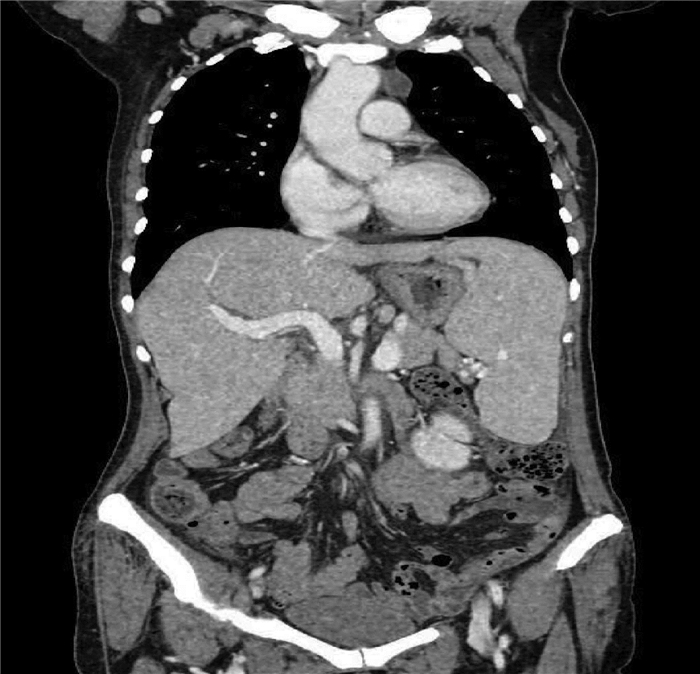

Liver biopsy diagnosis of hepatic extramedullary hematopoiesis: A case report